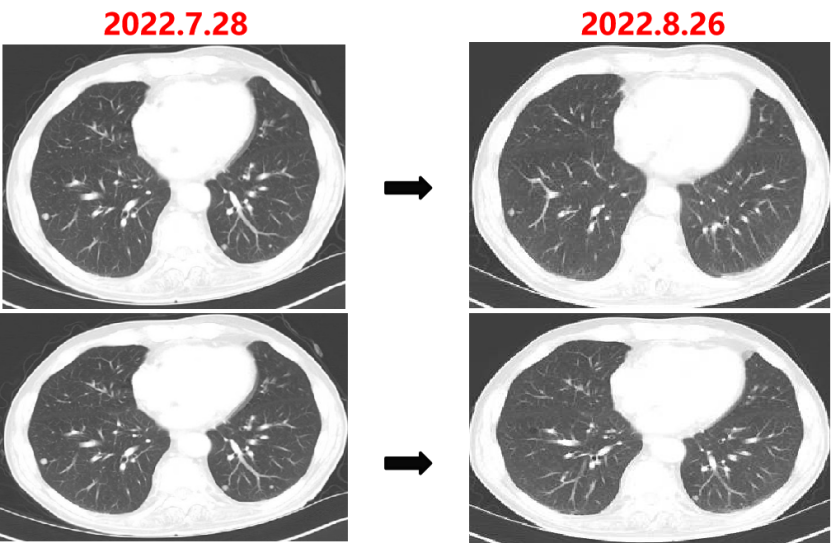

Q1 对于晚期转移性结直肠癌患者,目前,免疫治疗在新辅助治疗中的研究进展和临床应用如何? 结直肠癌是全球第三大肿瘤,转移性结直肠癌的5年生存率只有14%,治疗手段包括手术、化疗、放疗和靶向治疗等。免疫检查点抑制剂的出现也改写诊疗指南。大肠癌dMMR/MSI-H亚型约占所有病例的15%和mCRC病例的5%。由于dMMR/MSI-H的高突变率,肿瘤具有高免疫原性,使其能够激活免疫系统的抗肿瘤作用。 KEYNOTE-177这是一项三期国际开放标签随机对照研究,入选MSI-H/dMMR的IV期结直肠癌患者,比较帕博利珠单抗治疗(200 mg,每3周1次,最多35个周期)与在一线中使用或不使用抗VEGF或抗EGFR单克隆抗体的标准双药化疗,主要终点是PFS和OS。结果显示,帕博利珠单抗组患者的中位PFS时间为16.5个月 VS 8.2个月;3年PFS率分别为42% VS 11%,3年OS率分别为61% VS 50%。帕博利珠单抗组ORR为45.1%(20例完全缓解,49例部分缓解),化疗组为33.1%(6例完全缓解,45例部分缓解);帕博利珠单抗组83.5%的患者至少维持缓解了2年;在化疗组中,只有33.6%的患者缓解持续时间≥2年。KEYNOTE-177研究证实了帕博利珠单抗可以作为MSI-H或dMMR患者的一线标准治疗。 在2021版CSCO结直肠癌诊疗指南中,MSI-H结直肠癌姑息一至三线均推荐免疫治疗,其中帕博利珠单抗作为一线治疗的一级推荐;CheckMate-142研究选择MSI-H/dMMR转移性结直肠癌患者,单免后线vs双免后线vs 双免一线:ORR 39% vs 65% vs 71%,DCR 69% vs 81% vs 84%,一线双免完全缓解率为13%。结果说明双免好于单免,一线好于后线。CheckMate-142研究具有划时代意义,它将免疫治疗从后线前移到一线。 COMMIT研究是一项前瞻随机开放标签的三期临床研究,评估了阿特珠单抗单药治疗对比mFOLFOX6(氟尿嘧啶、奥沙利铂、亚叶酸钙)+贝伐珠单抗+阿特珠单抗一线治疗dMMR或MSI-H转移性结直肠癌的疗效和安全性,目前该试验还在进行中。未来该项研究的结果将回答对于MSI-H晚期结直肠癌,在一线免疫治疗的基础上联合化疗和抗血管靶向药物是否可以进一步提高免疫治疗的疗效。 CheckMate 8HW是另一项随机对照三期临床研究,在一线治疗dMMR或MSI-H转移性结直肠癌中,比较纳武利尤单抗单药、纳武利尤单抗联合伊匹木单抗以及研究者选择的化疗这3种方案的疗效。这项研究将头对头地比较对于MSI-H晚期结直肠癌双免联合是否优于单免的疗效。 Q2 对于MSI-H/dMMR型局部晚期结直肠癌(LACRC),新辅助免疫治疗探索的进展与应用前景如何?有哪些潜在预测疗效的生物标志物? 对于MSI-H/dMMR型局部晚期结直肠癌患者,新辅助免疫治疗可以在肿瘤手术前,提前使患者的免疫系统识别肿瘤细胞,从而使患者的免疫系统更好地产生免疫应答。目前结直肠癌新辅助治疗的探索均为二期研究,探索模式多为双免疫或免疫联合化疗方案,直肠癌多为免疫联合放化疗(同步或序贯)的模式。 NICHE研究是探索纳武利尤单抗联合伊匹木单抗用于Ⅰ-Ⅲ期结肠癌新辅助治疗的二期临床研究,研究共纳入40例结肠癌患者,其中21例为dMMR,20例为pMMR(1例患者同时为pMMR和dMMR),81%的dMMR患者和40%的pMMR患者为临床Ⅲ期结肠癌。患者在接受首次免疫治疗后不迟于6周内接受结肠癌手术,dMMR结肠癌缓解率100%,其中完全缓解的患者占60%,MPR为95%;pMMR治疗组27%的患者也对免疫治疗产生了良好的应答。 NICHE2研究,纳入更多患者,探寻非转移性dMMR结直肠癌患者双免治疗(伊匹木单抗+纳武利尤单抗)的疗效,主要终点为安全性,3年无病生存期。结果显示:MPR率95%,PCR率67%,中位随访13.1个月后没有患者出现疾病复发,毒性可耐受。 NCT04165772研究(前瞻性,单臂,Ⅱ期研究),Ⅱ期和Ⅲ期患者接受新辅助dostarlimab(多塔利单抗)共6个月,结果显示CCR率为100%。 PICC研究是特瑞普利单抗联合或不联合塞莱昔布新辅助治疗错配修复蛋白缺陷或微卫星高度不稳定的局部进展期结直肠癌的双臂随机Ⅱ期临床试验,结果显示完全缓解率高达88%,进一步表明dMMR结直肠癌免疫疗效惊人,潜在替代放化疗及手术。 对于MSI-H或dMMR结直肠癌,NCCN结直肠癌指南中,新辅助治疗增加纳武利尤单抗±伊匹木单抗或帕博利珠单抗单药方案;转化治疗可以选择双免疫或单免疫用药方案。 但并非所有患者都能从免疫治疗中获益,故筛选免疫治疗的疗效预测生物标志物将显得尤为重要。近年来研究主要集中在包括MSI-H、PD-L1过表达、TMB-H(TPS3645)、POLE或POLD1基因突变、PI3K/AKT/mTOR通路、新抗原(身份和数量)、免疫系统状态(免疫细胞特征、T细胞受体相关)等。 Q3 您如何看待对于临床中MSI-H/dMMR 转移性结直肠癌患者使用免疫治疗,部分患者仍然会出现耐药问题? Q4 晚期结直肠癌通常预后相对较差、患者生存期不长,依然是我国困扰结直肠肿瘤治疗的瓶颈问题,但有治愈的可能,此时临床医生制定正确合理用药方案尤为重要。今年上半年发布的CACA-RC指南推荐不适合强烈治疗患者应用曲氟尿苷替匹嘧啶片(TAS-102)联合贝伐珠单抗,作为晚期不可切除结直肠癌姑息一线治疗方案。请您谈谈该推荐治疗对我国晚期不可切除结直肠癌患者的临床治疗带来怎样的获益? 今年上半年CACA-RC指南推荐了不适合强烈治疗的患者应用TAS-102联合贝伐珠单抗作为不可切结直肠癌一线治疗方案,是在不可切除晚期结直肠癌一线治疗中石破天惊的一项突破。晚期mCRC的标准化疗方案在指南中是以奥沙利铂或伊立替康为基础的FOLFOX和FOLFIRI方案,在此基础上,可以根据基因分型联合西妥昔单抗或者贝伐珠单抗,但是依旧有部分患者身体状况无法耐受加强化疗,针对这一类患者的治疗方案选择非常有限,且预后情况并不理想。TAS-102+贝伐珠单抗治疗方案毒副反应相对较低,(临床试验提示比贝伐珠单抗联合卡培他滨效果好)疗效确切,在未来较长一段时间内,尤其是目前疫情肆虐,患者不方便住院治疗时,TAS-102可作为国内不适合强烈治疗的mCRC患者及老年患者的一线治疗优选方案,并为患者带来持续的、更优的生存获益。 二 病例分享 专家简介 王峰 教授 医学博士,副主任医师,硕士研究生导师 滨州医学院附属医院肿瘤科副主任 澳大利亚悉尼维斯迈医学中心访问学者 中华医学会放射肿瘤治疗学分会骨与软组织学组委员 中国临床肿瘤学会(CSCO)神经系统肿瘤专家委员会委员 山东省医师协会肿瘤精准医疗医师分会常务委员 山东省医师协会肿瘤放疗医师分会委员 山东省抗癌协会消化道肿瘤分会常务委员 山东省医学会咽喉肿瘤多学科联合委员会委员 山东省医学会烟草病学与戒烟多学科联合委员会委员 山东省健康管理协会消化道肿瘤防治分会常务委员 山东省医学会放射肿瘤学分会青年委员 山东省医学会妇科肿瘤多学科联合委员会委员 滨州市医学会放射肿瘤学专业委员会副主任委员 01 基本情况 (一)基本信息 患者男性,65岁,于2021-08-26第一次入滨州医学院附属医院风湿免疫科。 主诉:发作性右踝关节肿痛3年,再发1月。 查体:双足第一跖趾关节可见红肿,伴局部皮温升高。 既往史、个人史:既往脑梗死病史7年余,未遗留后遗症;有“膀胱结石”病史1年余,未系统诊治;有“痛风性关节炎”3年余,曾于滨州医学院附属医院风湿免疫科治疗。有高血压病史10年余,最高血压180/110mmHg,口服“吲达帕胺片”,血压控制可。 常规检查发现2次大便潜血阳性。 (二)辅助检查结果 1.肠镜检查 直肠、乙状结肠:直肠距肛门7cm可见一巨大溃疡型病变,表面溃烂,污秽苔,周边环堤样隆起,累及管腔1/3周圈,管腔无狭窄,于病变周边多点活检8块,质脆易出血;乙状结肠见一0.5cm*0.3cm息肉,余黏膜光滑,皱襞清晰,蠕动规律;肛管未见异常。降结肠、横结肠:横结肠见一0.3cm*0.4cm 0-IIa型息肉,表面粗糙,余黏膜光滑,血管纹理清晰,未见异常。 诊断:1.直肠Ca(进展期 溃疡型);2.结肠多发息肉——内镜下冷切除术+息肉摘除术。 2.胸部、上腹部未见明显异常。 直肠MR增强+DWI:直肠距肛缘约5.5cm处肠壁明显不均匀增厚,累及长度约6.0cm,呈等/长T1、等/稍长T2信号,T2压脂呈不均匀高信号,DWI呈高信号,ADC图信号减低,增强扫描呈明显不均匀强化,相应局部管腔狭窄,邻近浆膜面模糊,周缘可见小淋巴结。 02 治疗经过 2021-09-08:于全麻下行全直肠系膜切除+末端回肠预防造瘘术。 术中见:肝脏、胃、腹壁等无转移性结节。肿块位于腹膜返折处,活动度差,侵及浆膜。肠周见明显散在肿大淋巴结。 术后病理:直肠下段中分化腺癌,侵犯外膜下脂肪组织,肿瘤出芽分级(高级别,Bd3),侵犯神经侵犯,未见确切脉管内癌栓;两侧手术切缘、环周切缘及标记切缘内均未查见癌累及,肠周淋巴结内未查见转移癌(0/17)。pTNM分期:pT3N0Mx。免疫组化结果:CK(+),MSH2(+),MSH6(+),MLH1(+),PMS2(+),MDR-1(3+),HER2(3+),P53(3+),Ki-67阳性率约70%。 术后诊断: 1.直肠癌II(pT3NOMO)期术后; 2.结肠多发息肉术后; 3.痛风性关节炎; 4.高血压病(3级 很高危); 5.脑梗死。 CSCO指南: 2021-10-04至2022-06-03:FOLFOX方案化疗10周期(奥沙利铂150mg d1+氟尿嘧啶 0.7g d1+4.4g civ);术后预防性放射治疗DT5000cGy/25f,同步卡培他滨。 2021-11-25至2021-12-06:尿培养提示肺炎克雷伯菌感染,结合泌尿外科、感染科会诊意见,给予左氧氟沙星抗感染治疗。 2022-06-12 肺无法穿刺活检。 基因检测示:(直肠)KRAS/BRAF/NRAS/PIK3CA 基因均未检出突变。伊立替康UGT1A1基因检测结果:非风险基因型。 CSCO指南: 2022-06-20:西妥昔单抗联合FOLFIRI方案治疗(西妥昔单抗900mg d1,伊立替康320mg d1,氟尿嘧啶0.7g iv 4.3g civ)。 2022-07-06:骨髓抑制、腹泻,西妥昔单抗联合FOLFIRI方案治疗(西妥昔单抗900mg d1,伊立替康280mg d1,氟尿嘧啶0.7g iv 4.3g civ)。 疗效对比: 循证依据: C-TASK FORCE研究:首个证实TAS-102联合贝伐珠单抗治疗mCRC的疗效及安全性研究。TAS-102联合贝伐珠单抗是难治性mCRC患者潜在治疗选择,更多临床获益有待进一步研究。 TAS-102联合贝伐珠单抗治疗mPFS时间和mOS时间分别为5.6个月和11.2个月。 TAS-102联合贝伐珠单抗不良反应主要为血液学毒性。 日本大样本RWS:TAS-102和瑞戈非尼不同排序的回顾性研究。 日本大样本RWS:TAS-102单药较瑞戈非尼单药,可显著延长mOS,降低AE。 日本大样本RWS:两药序贯疗效优于单药,且≥65岁先用TAS-102获益更显著。 日本大样本RWS:TAS-102序贯瑞戈非尼组持续治疗时间更长。 2022-07-27至今 给予贝伐珠单抗联合TAS-102治疗期间复查CT评估SD,胃肠道反应不重,骨髓抑制Ⅰ度,耐受性尚可。 *本文仅代表专家观点,并经专家审校。